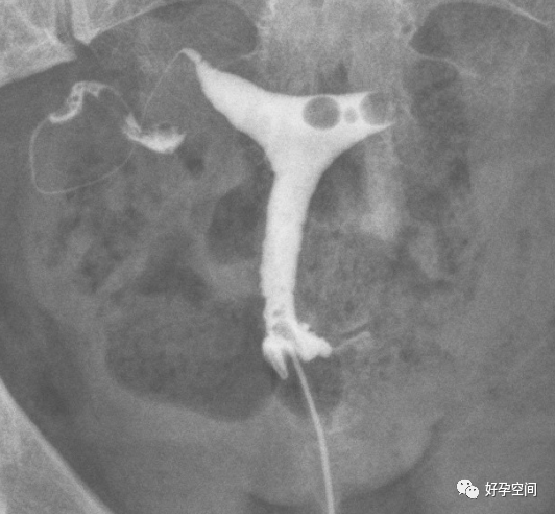

子宫相

输卵管相